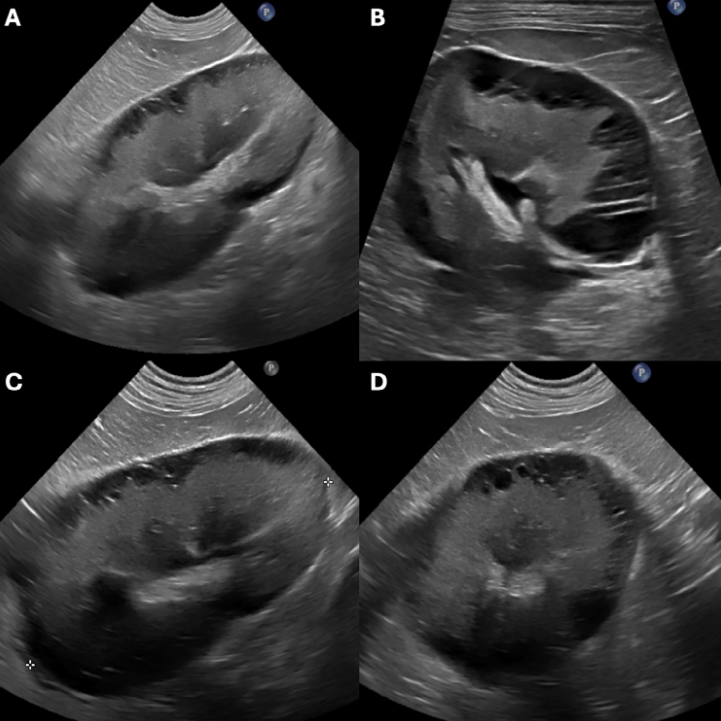

9세 래브라도 리트리버견에서 발생한 희귀 질환인 양측 신장 림프관 확장증에 대한 증례를 보고한다. 해당 환자는 질소혈증 및 양측 신장 비대로 내원하였으며, 초음파 검사에서 신장 피막 하에 다수의 낭성 병변이 관찰되었다. 이는 신장 림프관 확장증의 특징적인 소견으로 알려져 있다.

진단에는 초음파 검사가 유용하며, 특징적으로 신장 피막 하에 격벽을 가진 낭성 무에코 병변이 관찰된다. 도플러 검사 시 병변 내 혈류 신호는 나타나지 않는다. 이는 다른 신장 질환과의 감별에 중요한 단서가 된다. 컴퓨터 단층 촬영(CT)이나 자기 공명 영상(MRI)과 같은 다른 영상 진단 기법도 활용될 수 있다.

| 개에서의 신장 림프관 확장증 초음파 소견 특징적인 원형 피막하 격벽/낭성 무에코성 액체 축적과 혈류 신호 부재가 신장 림프관 확장증을 다른 질환(요종, 다낭성 신장, 림프종, 수신증 등)과 구별하는 데 중요